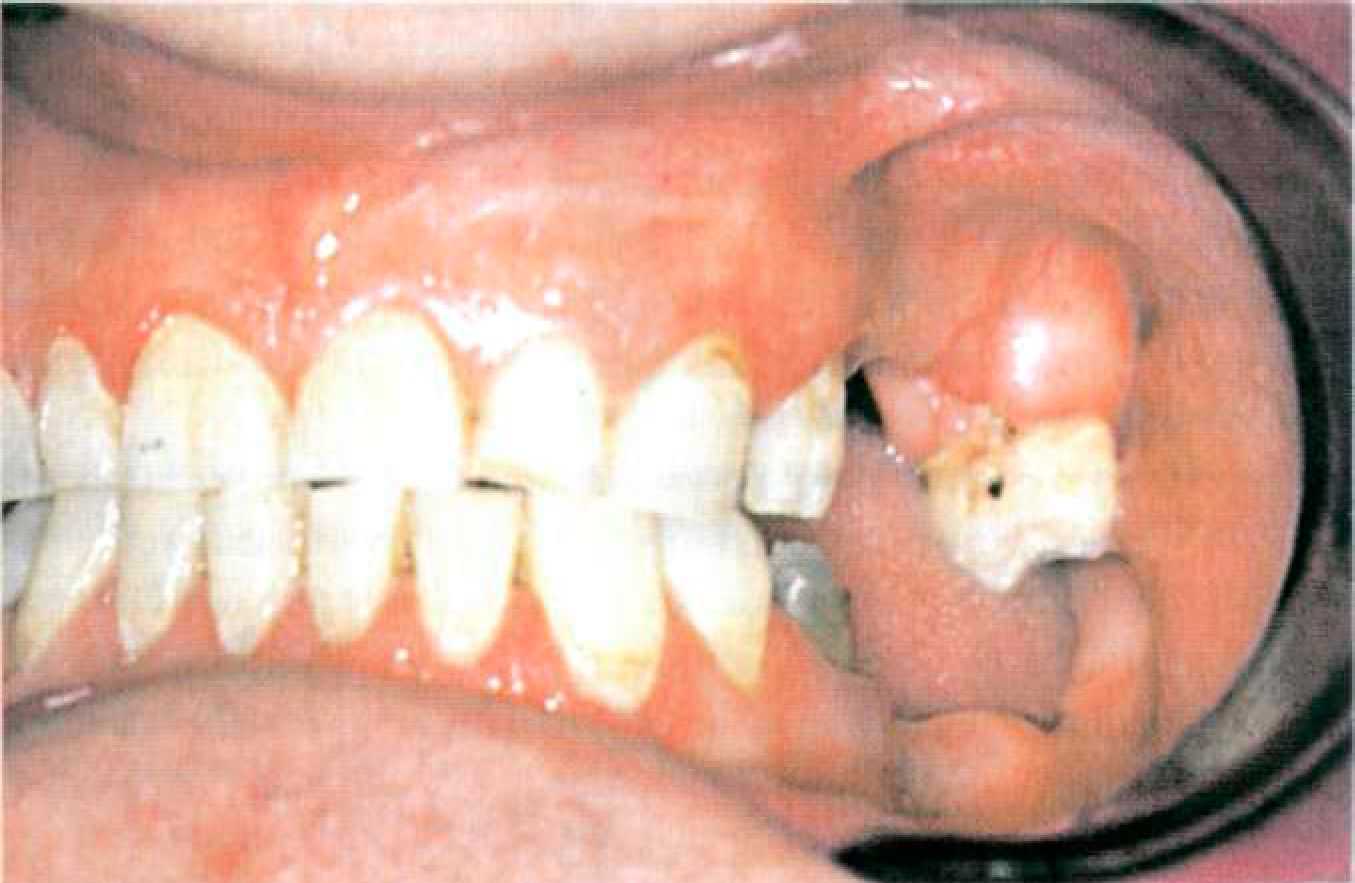

| КЛИНИКО-ЛАБОРАТОРНЫЕ ЭТАПЫ ИЗГОТОВЛЕНИЯ КОМБИНИРОВАННОГО ПРОТЕЗА С ЖЕСТКИМ ЗАМКОВЫМ КРЕПЛЕНИЕМ Этап 1. Протезирование комбинированными протезами начинается с обследования, постановки диагноза, составления плана лечения. Для составления плана лечения изготавливают диагностические модели для оценки вертикального расстояния между зубными рядами, длины опорных зубов, плоскости окклюзии, топографии дефекта. Далее определяют центральную или привычную окклюзию, фиксируют модели в артикулятор для изучения пространства и места для расположения аттачмена между зубами-антагонистами (в случае использования экстракоронарного аттачмена). После выбора подходящего аттачмена проектируют конструкцию протеза на диагностических моделях. Для клинической ситуации, представленной на рисунке 103, было выбрано замковое крепление МК— 1. Предостережение. Последовательность клинико-лабораторных этапов приводится на примере замкового крепления МК—1. Для определения лабораторных этапов работы с другими замковыми креплениями используйте рекомендации фирмы-производителя.